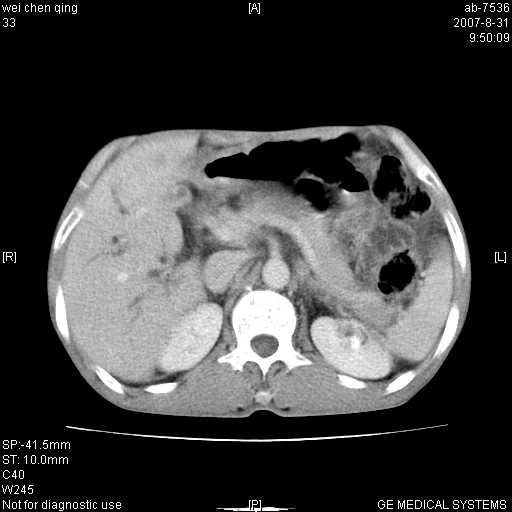

以下是引用zyyzzy在2007-8-31 14:34:00的发言:[br]该病人肝内胆管扩张,胆囊及胆总管未见明显扩张。在倒数第9层图像上可看到左右肝管结合部(肝总管)有软组织影,此处应薄层扫描。考虑肝总管占位(ca)、腹水。[br]